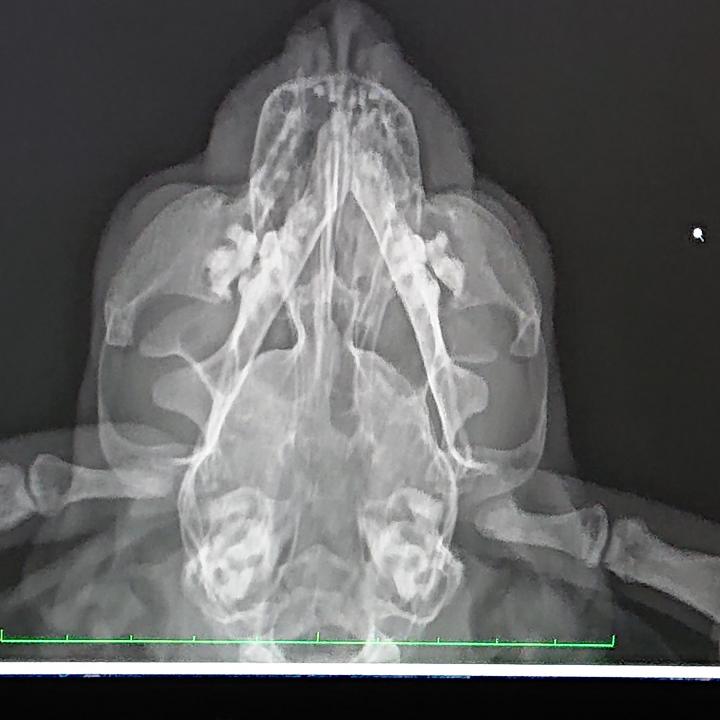

レントゲン、エコー、血液検査。

鼻がちょっと変な感じ。

感染症による蓄膿症?

腫瘍?

3人の先生に診てもらっても、腫瘍らしきものもないし、鼻を抜けた喉や肺は綺麗だと言うし…